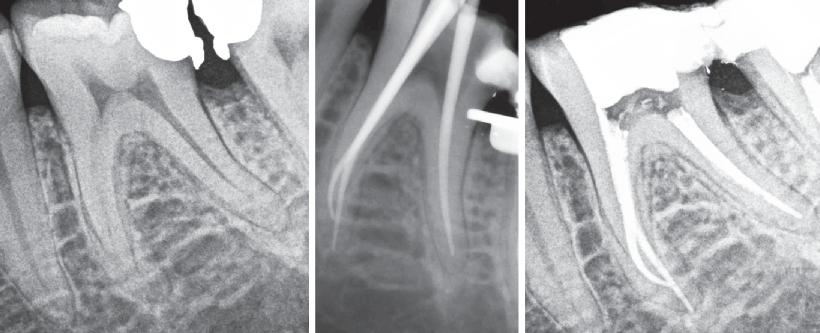

An orthopantomogram (OPG) revealed RL8 and LL8 were mesioangularly impacted and their roots were crossing both upper and lower white lines of the inferior alveolar canal (IAC). LL8 roots showed darkening of root at the level of IAC (Fig 1).

It was decided to request a Cone Beam CT to substantiate findings of the routine OPG in relation to the IAN.

CBCT revealed the following findings:

LL8: IAC was running buccal to roots of LL8 which had 3 roots (Fig 2).

RL8: IAC was seen running between the buccal root which was hooked mesially and lingual roots at its apex, vulnerable to surgical injury (Fig 3).